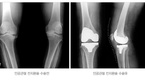

“아프지 않아서 가장 좋아요.” 무릎인공관절 수술을 받은 박모(67세, 여)씨는 무릎 통증이 사라진 것이 신기한 듯이 말했다. 통증이 없어지면서 얼굴도 한결 밝아진 모습이다. 인공관절수술은 연골이 닳아서 움직일 때마다 심한 통증으로 인해 정상적인 생활을 할 수